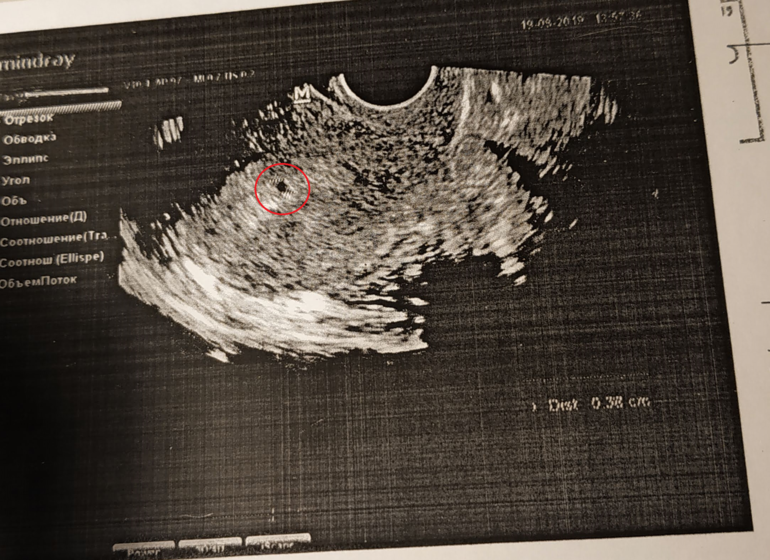

Здравствуйте, девочки. Разъясните мне, что на узи у меня увидели. Анэхогенное включение 3,8 мм. тесты отрицательные, хгч тоже отрицательно. А вот что на узи?) Узи делала где-то на 8-9 дпо. Видно ли вообще на таком сроке что-нибудь? Да и хгч должен ведь показать сразу

Грудь болит, живот тянет. Может киста какая?

День овуляции точно знаете? Вообще пя в матке видно на УЗИ после 1000 единиц ХГЧ. Я бы думала на полип какой-нибудь или что-то в этом роде.

При отрицательном ХГЧ это не беременность. Да и не увидели б на таком сроке. Посмотрела в инете возможные причины, вот что нашла : эндометриоз в полости матки, киста матки, узловая миома. Нужно смотреть в динамике, будет ли расти, как будет вести себя дальше.

Слишком кругло для полипа или кисты... Переделайте узи на 7-8дц. Если полип, чуть подсдуется-форму поменяет после месиков. Вообще лучше узи переделать у того, кто скажет что это